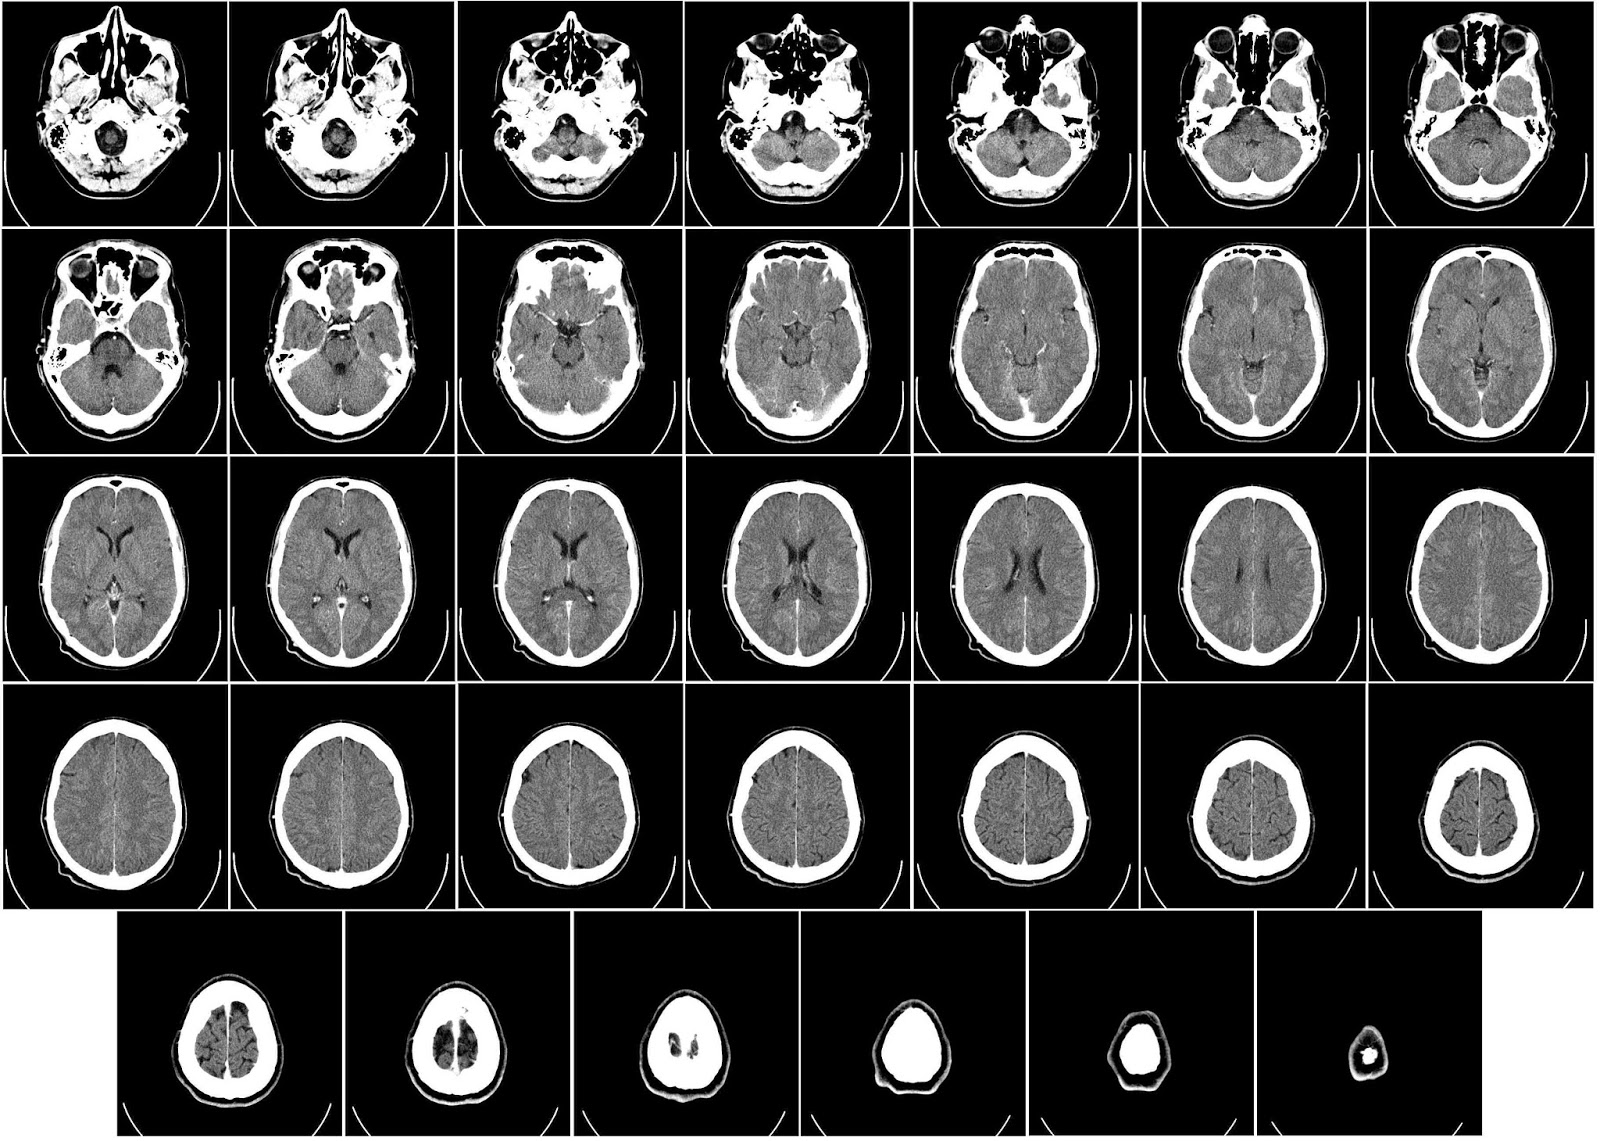

Anne Arundel Medical Center CT/MRI Ordering Guide

Anne Arundel Medical Center CT/MRI Ordering Guide Body Part Signs/Symptoms Exam to order Brain Trauma, CVA, Bleeding, This does not imply protocol standards for all the radiology facilities. appendicitis is suspected or if you have concerns about the colon, ... Read Content